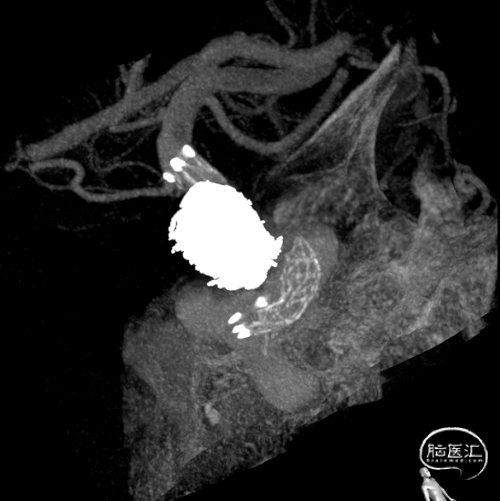

术后即刻影像及患者术后情况

标准正位

标准侧位

支架CT

术后CT

行正侧位造影及3D造影,全身肝素化后路图下将使用经塑形SL10微导管和prowler在0.14微导丝带领下超选进入动脉瘤和载瘤动脉,释放部分4.5*28支架,选用弹簧圈7枚栓塞动脉瘤,充分释放支架,造影复查显示动脉瘤被致密栓塞,载瘤动脉通畅。